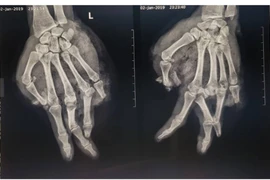

Sau khi sơ cứu và khâu vết thương tại cơ sở y tế địa phương, bệnh nhân được chuyển đến Bệnh viện Bạch Mai vì tổn thương vùng kín có dấu hiệu phức tạp. Tại đây, bệnh nhân được các bác sỹ chuyên khoa Phẫu thuật Tiết niệu và các chuyên khoa khác thăm khám, đánh giá tổn thương. Các bác sỹ đã phát hiện bìu trái của bệnh nhân sưng to, có khối máu tụ lớn lan xuống bẹn, kèm theo một vết gãy ở xương cẳng chân trái.

Hình ảnh siêu âm Doppler tinh hoàn cho thấy khối máu tụ lớn đã chèn ép, đẩy tinh hoàn lệch trục. Các bác sỹ đã nhanh chóng tiến hành phẫu thuật cấp cứu ngay trong đêm. Trong quá trình phẫu thuật, các bác sỹ Khoa Phẫu thuật Tiết niệu đã tìm thấy một mảnh dị vật bằng nhựa cứng, nghi là từ bình ga mini, cắm sâu trong bìu trái. Dị vật có kích thước khoảng 1x2cm, kèm theo nhiều máu cục.